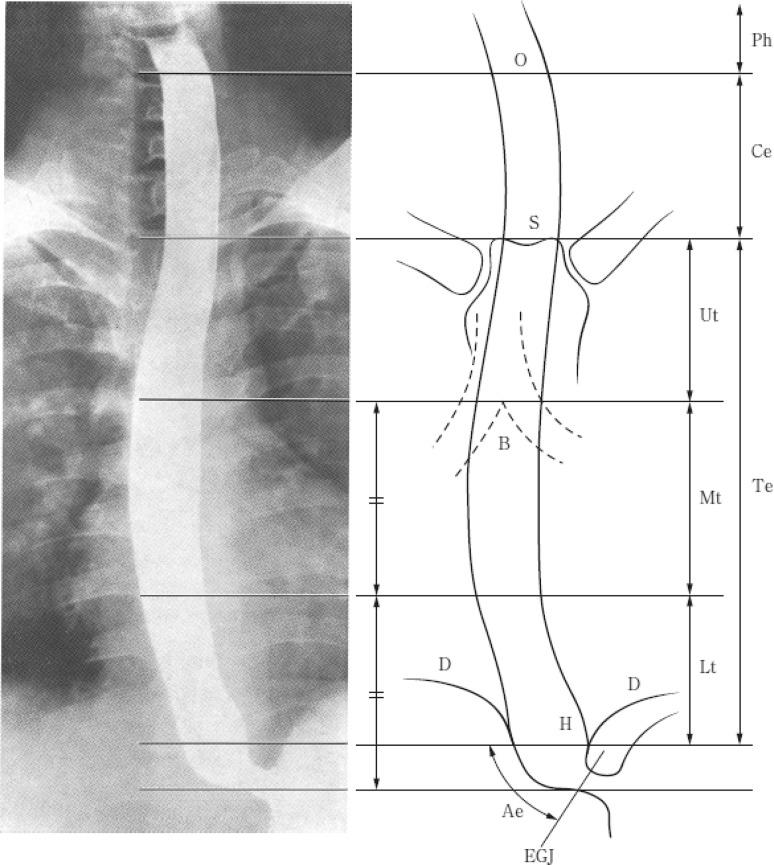

Japanese Classification of Esophageal Cancer, 11th Edition: part I.

Esophagus. 2017;14(1):1-36. doi: 10.1007/s10388-016-0551-7. Epub 2016 Nov 10.